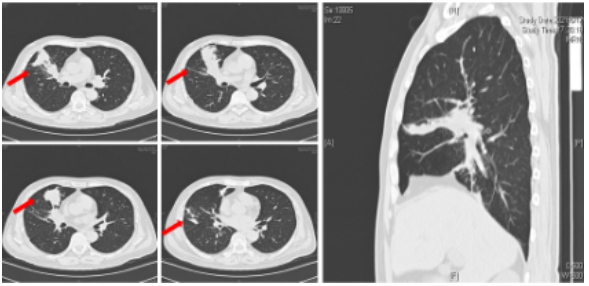

支气管镜在肺真菌病治疗中的应用主要有:①通畅气道:清除气道潴留物,解除机械阻塞。②冲洗引流:脓腔冲洗引流;液性病灶穿刺引流;炎症部位支气管冲洗;导管冲洗;穿刺引流。③局部用药:支气管冲洗、留置导管注药、药物缓释系统置入。病例:一名45岁男性因咳嗽、咳黄痰、呼吸困难持续5个月入院,患者胸部CT提示肿块引起的阻塞性肺不张(图3),但初步病理活检并未明确支持肿瘤诊断。这种不确定性可能与浅表取样有关,但不能完全排除肿瘤病变,使用硬质支气管镜检查缓解气道阻塞。术中见气道内白色肿块,该肿块松散地附着在支气管壁上(图4),镊子取出肿块时出血极少。肿块的组织学检查显示慢性化脓性炎症和肉芽肿形成、提示新型隐球菌感染。通过宏基因组二代测序证实了BALF中新生梭菌的存在。同时,血清隐球菌荚膜抗原检测结果呈阳性,氟康唑抗感染后痊愈。注:A:右主支气管和右中支气管有肿块,右下叶不张;B:右主支气管肿块消失,肺复张;C:右主支气管肿块完全消失和完全肺复张。图源:Medicine (Baltimore), 2024, 103(12):e37455.注:A:硬质支气管镜检查前软性支气管镜检查,显示右侧主支气管有肿块,导致闭塞;B:硬质支气管镜检查3天后软性支气管镜检查,证明成功从右侧主支气管中切除肿块。图源:Medicine (Baltimore), 2024, 103(12):e37455.隐球菌病胸部CT大部分表现为结节影,部分可有实变和坏死。支气管内隐球菌病导致的严重气道阻塞病例罕见,我们认为选择早期呼吸干预是一种理性的选择。首先,近一半的阻塞性支气管内隐球菌病患者对抗真菌药物反应不佳。其次,长期肺不张对肺复张构成挑战,可能导致永久性肺塌陷和肺功能受损,甚至最终导致肺实质感染和纤维化。软性支气管镜检查有助于区分内在性梗阻和外在压迫性,而硬质支气管镜检查可以更好地了解内在性梗阻性病变的性质,并提供一种气管内治疗手段。毛霉菌极易堵塞局部血管和支气管,病灶药物浓度低,单纯的全身药物治疗效果并不理想。近年来的研究发现两性霉素B局部给药,在抗真菌治疗方面会起到一定的辅助作用,包括雾化吸入、鞘内注射等,经支气管镜应用两性霉素B局部灌注对肺毛霉病可取得良好的效果。对于支气管被毛霉的菌丝体阻塞的患者,采用积极的介入治疗也可取得一定的效果,但应小心谨慎,防止出现大出血。各种介入治疗方法,包括两性霉素B局部灌注、冷冻治疗等,获得了不错的疗效。肺毛霉病的介入治疗必须具备全身麻醉、气管插管、预置球囊及有经验的呼吸内镜介入团队等。冷冻治疗建议在全麻气管插管方式下实施,出血风险高的患者还需要预置止血球囊。研究报道,10例肺毛霉病介入治疗患者均临床治愈,死亡0例。10例患者中应用冷冻探头冻取病灶8例,活检钳钳除病灶7例,套器套治疗2例,异物钳钳取病灶2例。介入和治疗经支气管镜直接局部灌注同步进行,1次/周,共1~6次。冷冻治疗的过程中3例患者预置球囊防止支气管内出血。10例患者中4级出血1例,3级出血2例,2级出血4例,3例患者无出血。支气管内出血均在5~10 min停止,术后少量痰中带血3~4天,术后气胸0例。牟向东教授团队在应用全身+局部治疗肺毛霉病的同时联合气管镜下介入技术清除阻塞气道和血管脓栓,并且在导航和超声定位下局部精准灌注两性霉素B,提高了肺组织内的药物浓度,降低了全身用药带来不良反应的概率,获得了显著的临床疗效,灌注后患者亦无明显不良反应(图5-图8)。注:右肺中叶和右肺下叶内基底段可见多发斑片影和片状肺内渗出实变影(箭头所示)。图源:https://www.btch.edu.cn/tszl/zbzx/fzjbzzzx/zb15blfx/91912.htm注:病理显示坏死组织内大量毛霉菌丝,并可见菌丝侵袭血管。